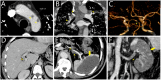

Figures